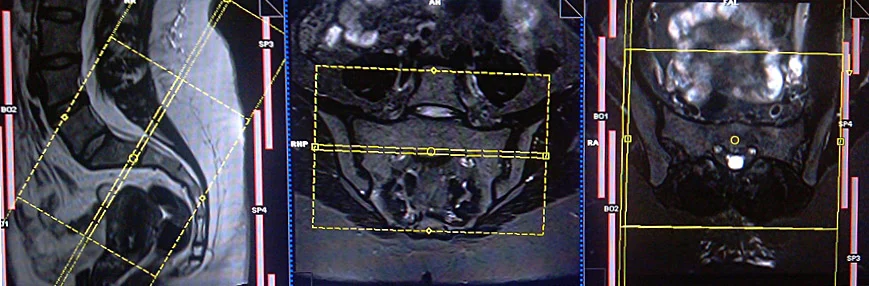

CASE STUDY NO.1

Coronal planning

Axial planning